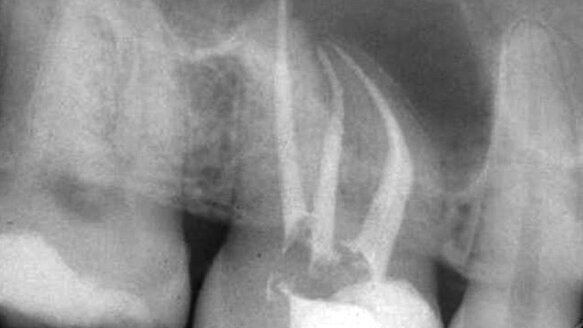

In the meantime, critical thinking would clearly demonstrate that relieved reamers (Fig. 3) are not only good for glide path creation but work far more safely when used for the entire shaping procedure. Stainless-steel relieved reamers are quite effective at recording the curvatures of a canal.2 Unlike NiTi, they do not snap back to the straight position, a property that increasingly distorts the apical end of curved canals as the tip size and taper of the instruments increase.

The greater stiffness of stainless steel is compensated for by the relieved reamer design, never exceeding a 02 taper and routinely straightening the coronal curve prior to the use of larger-tipped instruments. Used either in a tight watch-winding stroke or in a 30-degree reciprocating handpiece (Fig. 4), the tip of the instruments confined to such a short arc of motion always stay centered in the canal. As long as patency is maintained, these relieved reamers will not deviate from the original pathway. Patency3 is maintained by going 0.5 mm beyond the constriction through a 25 relieved reamer, a technique that is easy to master and is completely predictable in its results.

Without critical thinking, one will never learn that reamers are safer, more efficient and more effective than K-files. Without learning the superiority of reamers, one will never learn that relieved reamers are superior to non-relieved reamers. If one does not use reamers, one will not be exposed to the advantages of non-distorted shaping using a 30-degree reciprocating handpiece. Without the exposure to a 30-degree reciprocating handpiece, one will never appreciate the absence of torsional stress and cyclic fatigue4 that plagues rotary NiTi, leading to unpredictable separation. And, without the appreciation that instruments will simply not break, one will not confidently shape canals to the larger dimensions that are often required to ensure proper debridement and irrigation. For examples of cases done with relieved reamers in a reciprocating handpiece, see Figures 5–7.